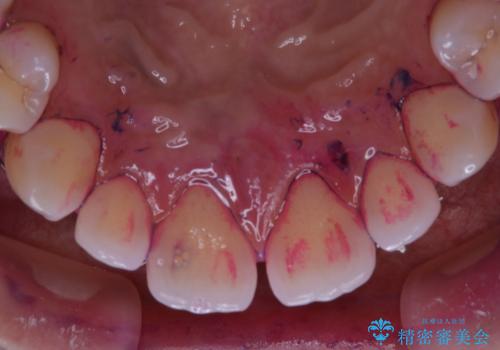

一見きれいに見える歯でも、染め出し(歯垢染色液)を使うとこのように歯と歯茎の境目や、歯と歯の間などに磨き残しがあることがわかります。歯磨きには、いつも気をつけているから磨き残しはナシと思っていても、実際完璧に磨ききることはなかなか難しいです。歯科医院にて、専門の機械で定期的なPMTCを行うことが大切です。